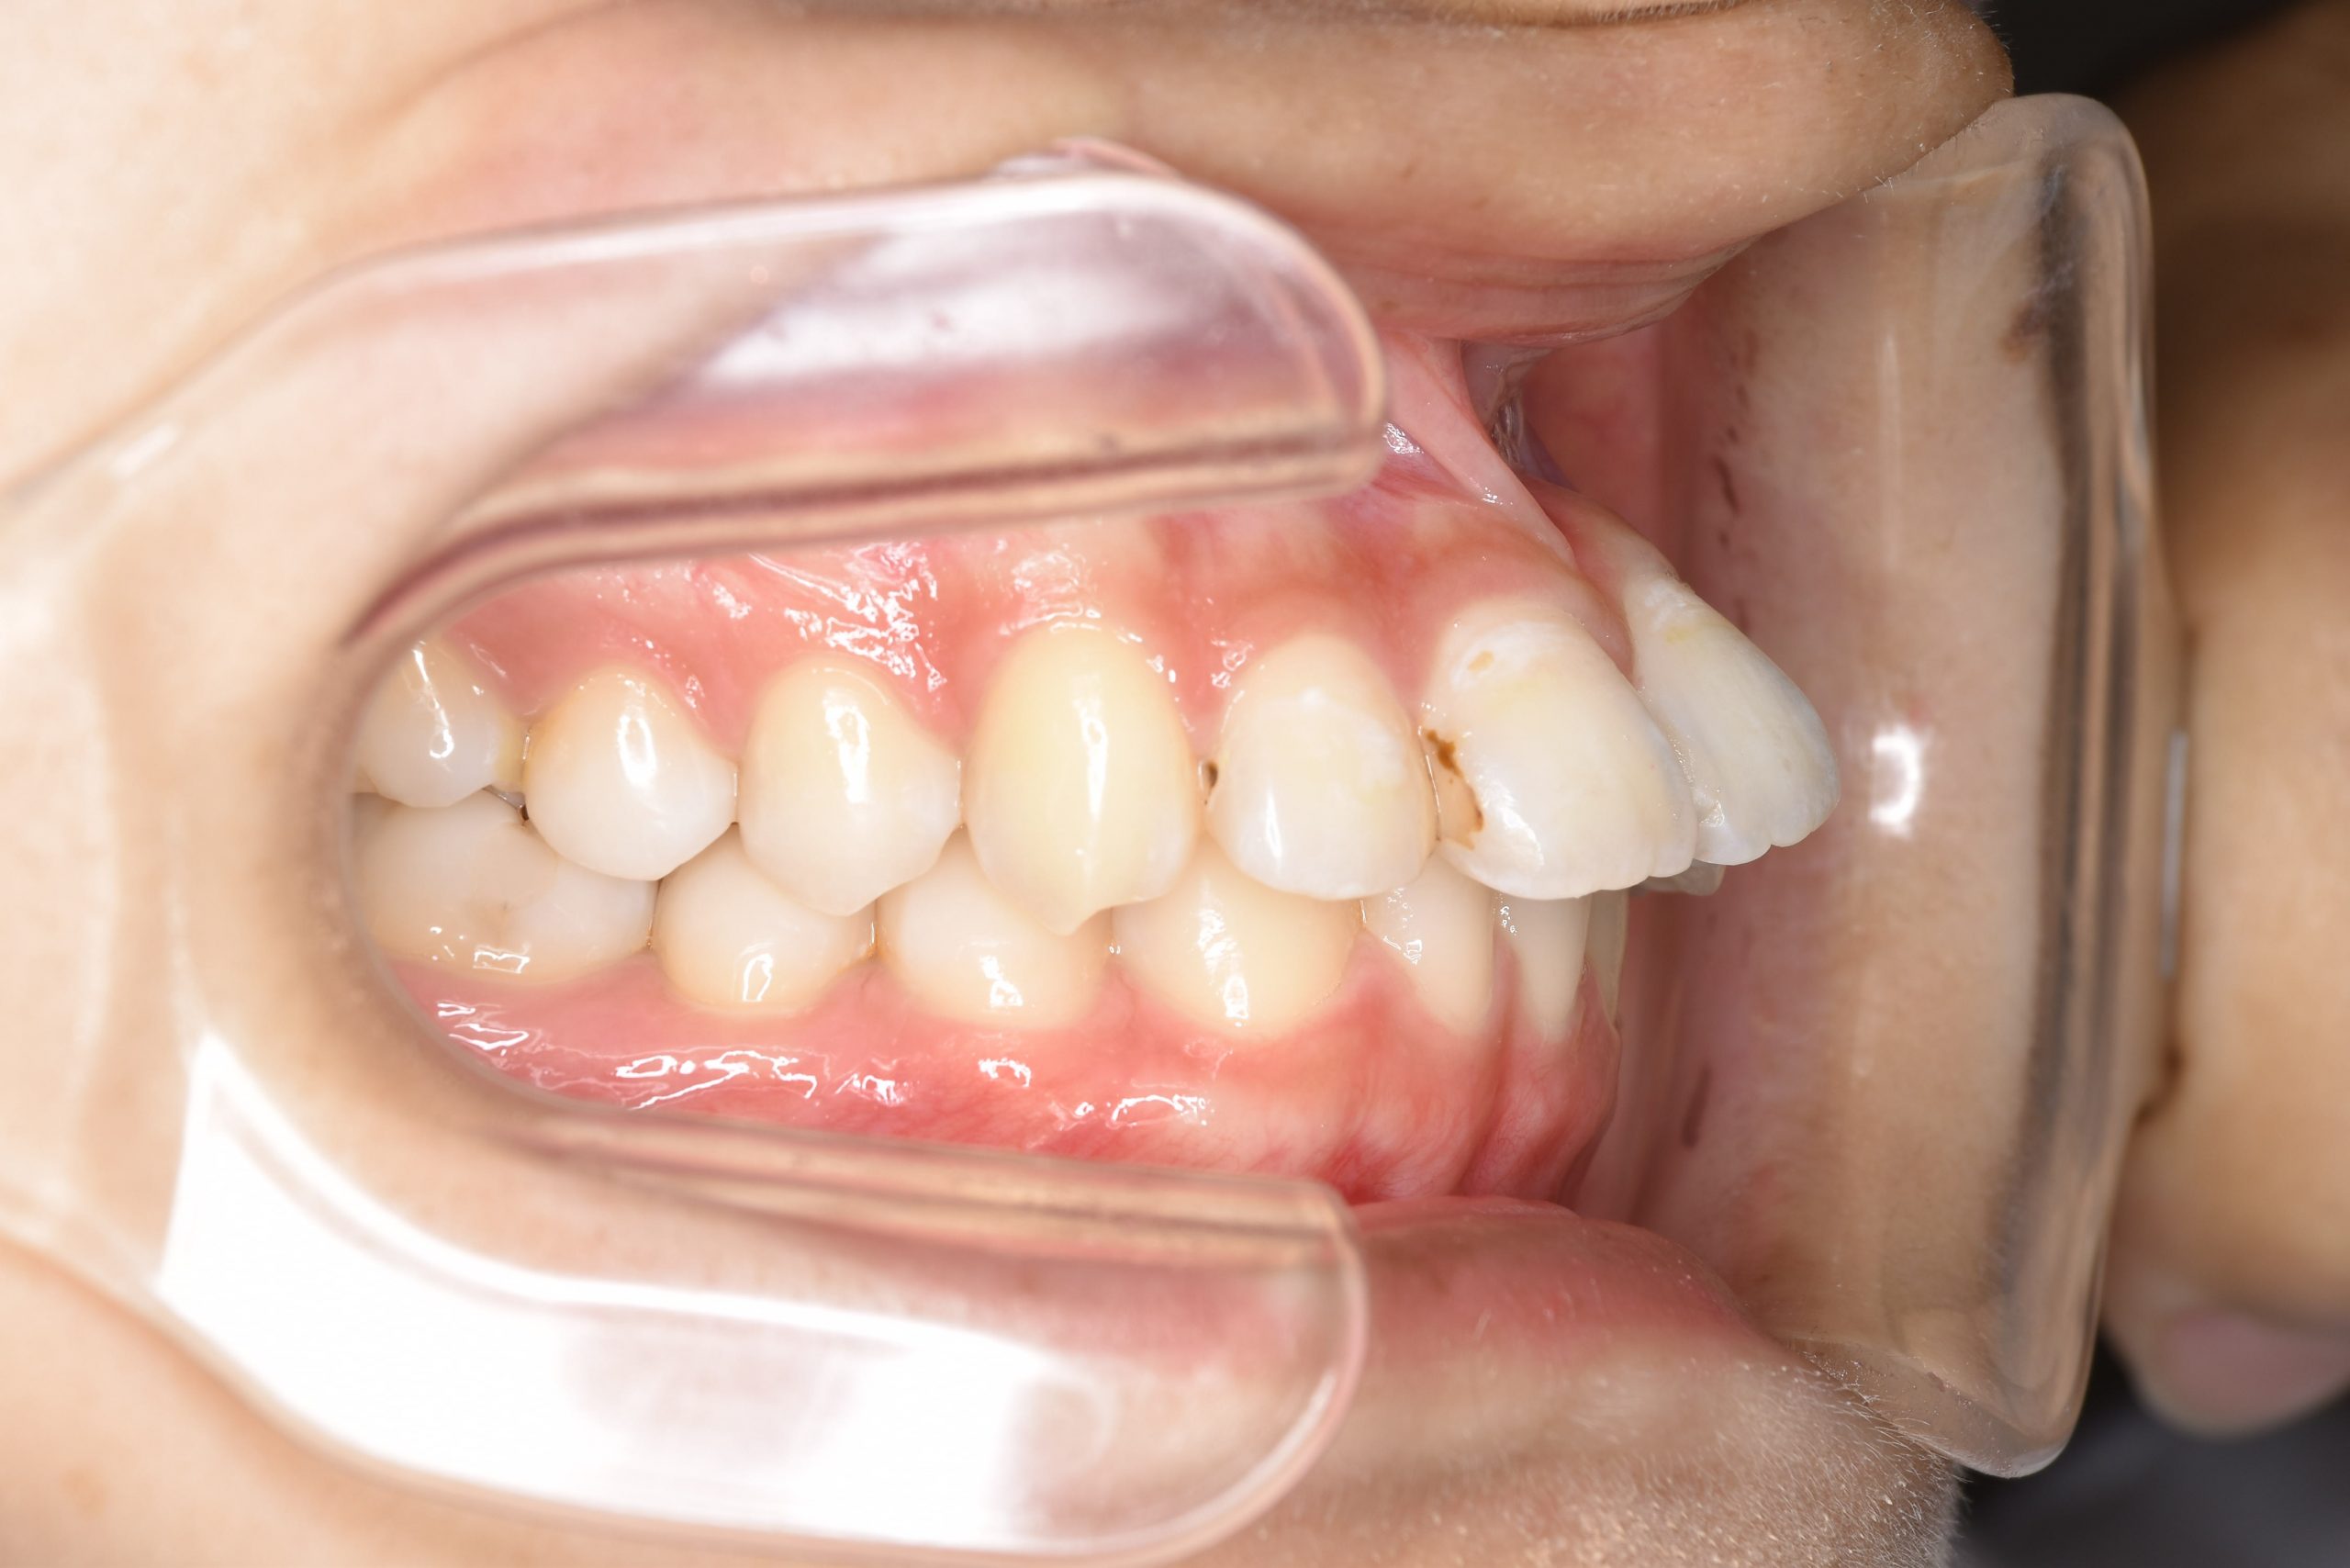

ビフォー

ワイヤー矯正治療|症例_009

主訴 出っ歯

施術内容 MSEと下顎リンガルアーチを用いて上下顎骨を拡大した。

その後マルチブラケット装置とミニインプラントを用いて非抜歯で歯牙を配列した。

下顎前歯が1本先天性欠損であったが、良好な咬合を獲得した。口元の突出感と鼻閉症状は改善された。